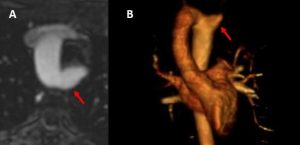

An aberrant subclavian artery usually causes an aortic diverticulum, or outpouching. Depending on its location, the artery might compress the esophagus or the trachea. It is unknown how many of these dilated portions of the artery result in rupture. Most literature seems to find a low number. Also, it could be that as we perform more imaging, we are finding more asymptomatic cases.

As this is an uncommon diagnosis, clinical suspicion is key. Incidental diagnosis with chest x-ray or CT scan is not unusual. Deliberate investigations include barium swallow and chest imaging. Imaging can include echocardiography, CT or MR. There are reports of a pulsatile mass visualized on upper endoscopy.